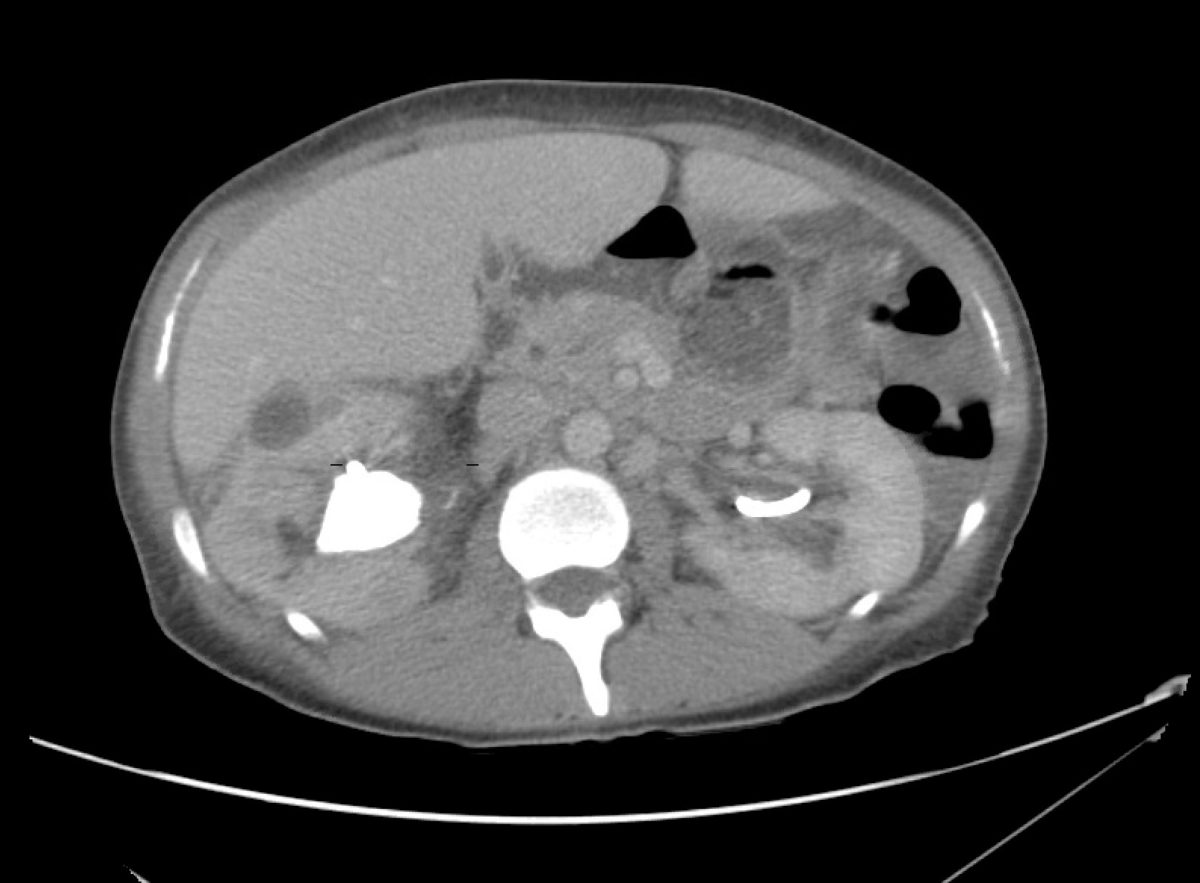

From radiologycases.my

Emphysematous pyelonephritis Radiology Cases Pyelo Nephr Itis management of pyelonephritis in adults. Learn about symptoms and treatment here. Pyelonephritis is generally a complication of an. A kidney infection (pyelonephritis) can be unpleasant, but it will usually improve if treated promptly. A urinary tract infection is described by location: If not treated properly, an infection can cause lasting damage to the kidneys. acute pyelonephritis is a. Pyelo Nephr Itis.